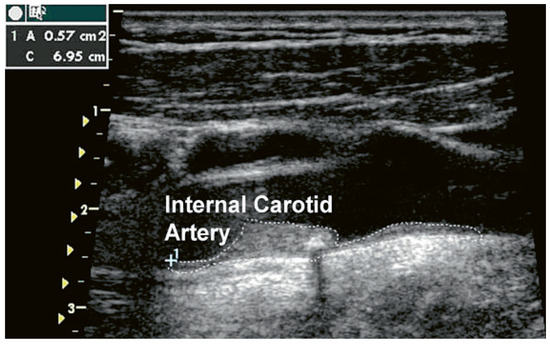

Cardiovascular Risk Prediction with Ultrasound

by Michèle Depairon, Roger Darioli and Michel Romanens

Cardiovasc. Med. 2010, 13(9), 255; https://doi.org/10.4414/cvm.2010.01523 - 15 Sep 2010

This paper addresses primary care physicians, cardiologists, internists, angiologists and doctors desirous of improving vascular risk prediction in primary care. Many cardiovascular risk factors act aggressively on the arterial wall and result in atherosclerosis and atherothrombosis. Cardiovascular prognosis derived from ultrasound imaging is, however, excellent in subjects without formation of intimal thickening or atheromas. Since ultrasound visualises the arterial wall directly, the information derived from the arterial wall may add independent incremental information to the knowledge of risk derived from global risk assessment. This paper provides an overview on plaque imaging for vascular risk prediction in two parts: Part 1: Carotid IMT is frequently used as a surrogate marker for outcome in intervention studies addressing rather large cohorts of subjects. Carotid IMT as a risk prediction tool for the prevention of acute myocardial infarction and stroke has been extensively studied in many patients since 1987, and has yielded incremental hazard ratios for these cardiovascular events independently of established cardiovascular risk factors. However, carotid IMT measurements are not used uniformly and therefore still lack widely accepted standardisation. Hence, at an individual, practicebased level, carotid IMT is not recommended as a risk assessment tool. The total plaque area of the carotid arteries (TPA) is a measure of the global plaque burden within both carotid arteries. It was recently shown in a large Norwegian cohort involving over 6000 subjects that TPA is a very good predictor for future myocardial infarction in women with an area under the curve (AUC) using a receiver operating curves (ROC) value of 0.73 (in men: 0.63). Further, the AUC for risk prediction is high both for vascular death in a vascular prevention clinic group (AUC 0.77) and fatal or nonfatal myocardial infarction in a true primary care group (AUC 0.79). Since TPA has acceptable reproducibility, allows calculation of posttest risk and is easily obtained at low cost, this risk assessment tool may come in for more widespread use in the future and also serve as a tool for atherosclerosis tracking and guidance for intensity of preventive therapy. However, more studies with TPA are needed. Part 2: Carotid and femoral plaque formation as detected by ultrasound offers a global view of the extent of atherosclerosis. Several prospective cohort studies have shown that cardiovascular risk prediction is greater for plaques than for carotid IMT. The number of arterial beds affected by significant atheromas may simply be added numerically to derive additional information on the risk of vascular events. A new atherosclerosis burden score (ABS) simply calculates the sum of carotid and femoral plaques encountered during ultrasound scanning. ABS correlates well and independently with the presence of coronary atherosclerosis and stenosis as measured by invasive coronary angiogram. However, the prognostic power of ABS as an independent marker of risk still needs to be elucidated in prospective studies. In summary, the large number of ways to measure atherosclerosis and related changes in human arteries by ultrasound indicates that this technology is not yet sufficiently perfected and needs more standardisation and workup on clearly defined outcome studies before it can be recommended as a practice-based additional risk modifier. Full article

Show Figures

Figure 1